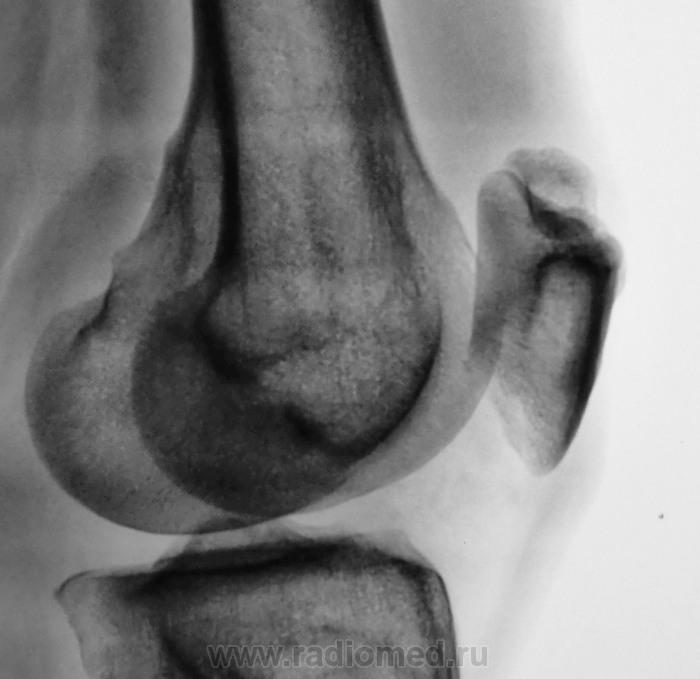

Травма. Направлен на рентгенографию коленного сустава

Такое развитие надколенника. Хотя может быть и травматический разрыв фиброзных сращений.

А, может быть просто пателла бипарцита?

Можно уточнение ? Край основной массы надколенника неровный, углы заострены и щель выглядит неравномерной -это обычная картина при удвоении надколенника ?

И мне это не понравилось. И по боковой - впечатление о смещении фрагмента.

Мужчина 39 лет, жалоб нет. Обратил внимание на разницу с другим коленным суставом (выпирает). Второй сустав на снимке без изменений. Травм утверждает, что не было.